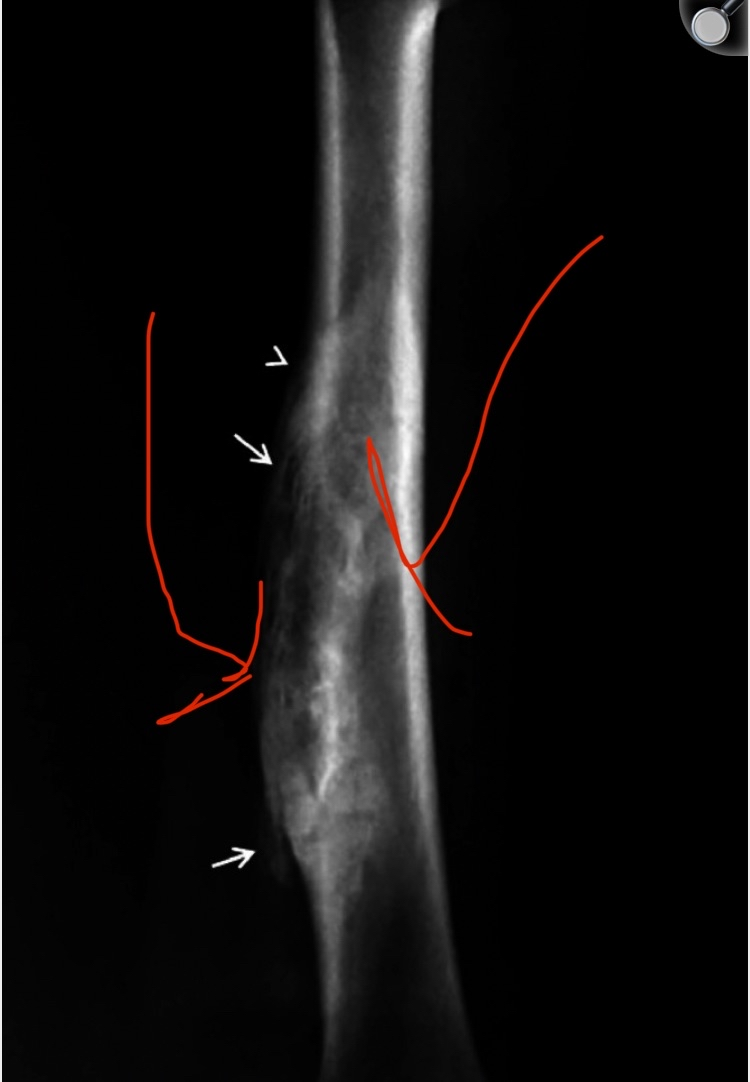

A case report on a Lacrosse player (this sport requires direct contact with the opponent to gain possession of the ball). The player reported pain in the area left exposed “between his shoulder and elbow pads”. Because the area was exposed, it was subjected to direct trauma, which caused a subperiosteal hematoma. Then it calcified and became bone (visible on X-ray). Oh my God, this conclusively proves my theory!! I previously explained that direct trauma to the bone causes a hematoma by rupturing the blood vessels between the periosteum and the bone, lifting the periosteum and forming a subperiosteal hematoma, which then forms new bone, exactly like this case, as described literally by the scientists.

Case Report: Ossified Subperiosteal Hematoma in the Humerus of a Lacrosse Player

So doesn’t this perfectly match what happens in bone smashing???